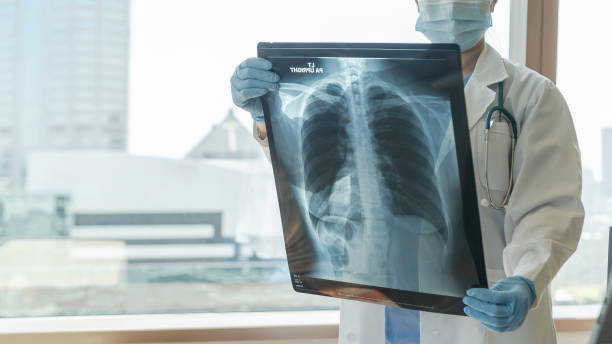

폐섬유화증은 폐조직 내 결손 및 염증에 의해 섬유화 과정이 일어나서, 건강한 폐조직이 염증과 섬유화에 대한 대체물질로 치환되는 질환입니다. 이로 인해, 섬유화된 조직은 신축성이 없고, 호흡기능이 저하됩니다. 따라서 다른 질병과 마찬가지로 초기에 적절한 치료를 받는 것이 중요하기 때문에 이번 시간에는 폐섬유화로 인한 증상들에 대해 정리해보겠습니다.